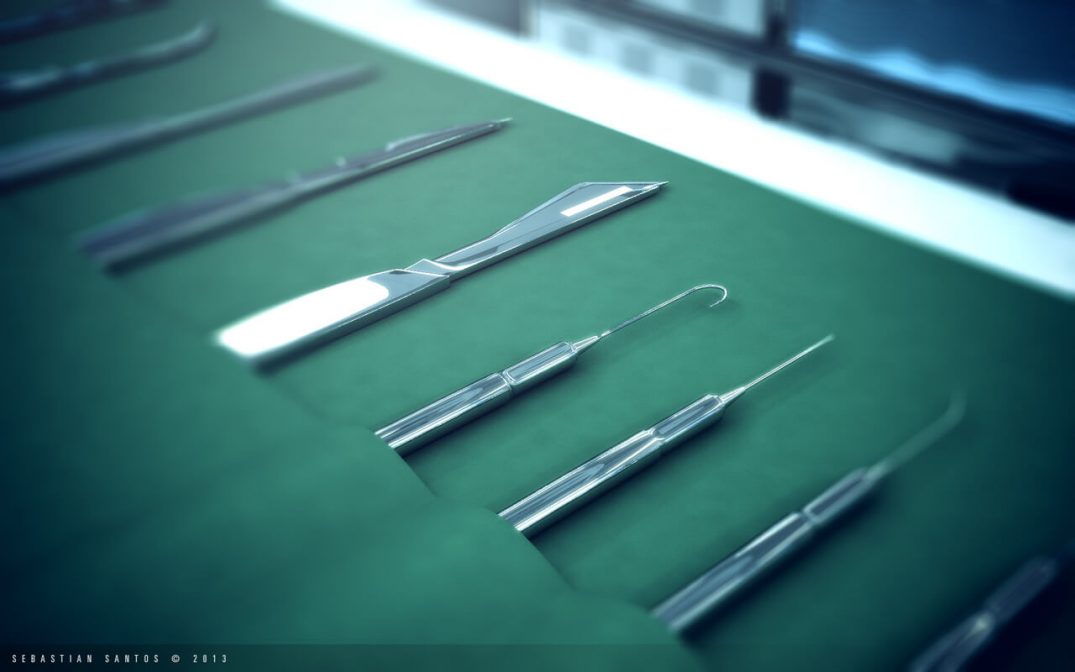

Ibu hamil yang kan melahirkan dapat memilih proses persalinannya. Proses persalinan dapat dilakukan dengan normal, operasi Caesar dan steril pasca caesar. Operasi caesar atau bedah caesar, dan disebut juga dengan seksio caesarea, merupakan persalinan dengan teknik pembedahan di perut sang ibu. Umumnya operasi ini dilakukan ketika proses persalinan normal seperti […]

Ibu hamil yang kan melahirkan dapat memilih proses persalinannya. Proses persalinan dapat dilakukan dengan normal, operasi Caesar dan steril pasca caesar. Operasi caesar atau bedah caesar, dan disebut juga dengan seksio caesarea, merupakan persalinan dengan teknik pembedahan di perut sang ibu. Umumnya operasi ini dilakukan ketika proses persalinan normal seperti […]

Ibu hamil 9 bulan tentunya menanti akan kelahiran buah hati. Kebanyakan ibu hamil menginginkan proses melahirkan normal. Namun dalam kasus tertentu perlu dilakukan tindakan operasi caesar khususnya jika terjadi masalah yang dapat mengancam nyawa ibu dan janin. Selain itu, ibu yang melahirkan caesar biasanya memerlukan waktu pemulihan yang lebih lama daripada […]

Ibu hamil 9 bulan tentunya menanti akan kelahiran buah hati. Kebanyakan ibu hamil menginginkan proses melahirkan normal. Namun dalam kasus tertentu perlu dilakukan tindakan operasi caesar khususnya jika terjadi masalah yang dapat mengancam nyawa ibu dan janin. Selain itu, ibu yang melahirkan caesar biasanya memerlukan waktu pemulihan yang lebih lama daripada […]